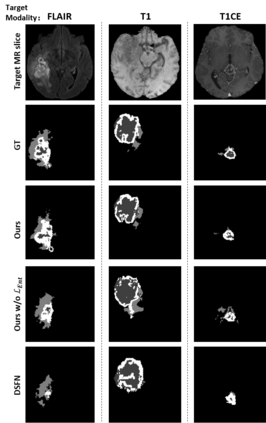

Unsupervised domain adaptation (UDA) between two significantly disparate domains to learn high-level semantic alignment is a crucial yet challenging task.~To this end, in this work, we propose exploiting low-level edge information to facilitate the adaptation as a precursor task, which has a small cross-domain gap, compared with semantic segmentation.~The precise contour then provides spatial information to guide the semantic adaptation. More specifically, we propose a multi-task framework to learn a contouring adaptation network along with a semantic segmentation adaptation network, which takes both magnetic resonance imaging (MRI) slice and its initial edge map as input.~These two networks are jointly trained with source domain labels, and the feature and edge map level adversarial learning is carried out for cross-domain alignment. In addition, self-entropy minimization is incorporated to further enhance segmentation performance. We evaluated our framework on the BraTS2018 database for cross-modality segmentation of brain tumors, showing the validity and superiority of our approach, compared with competing methods.